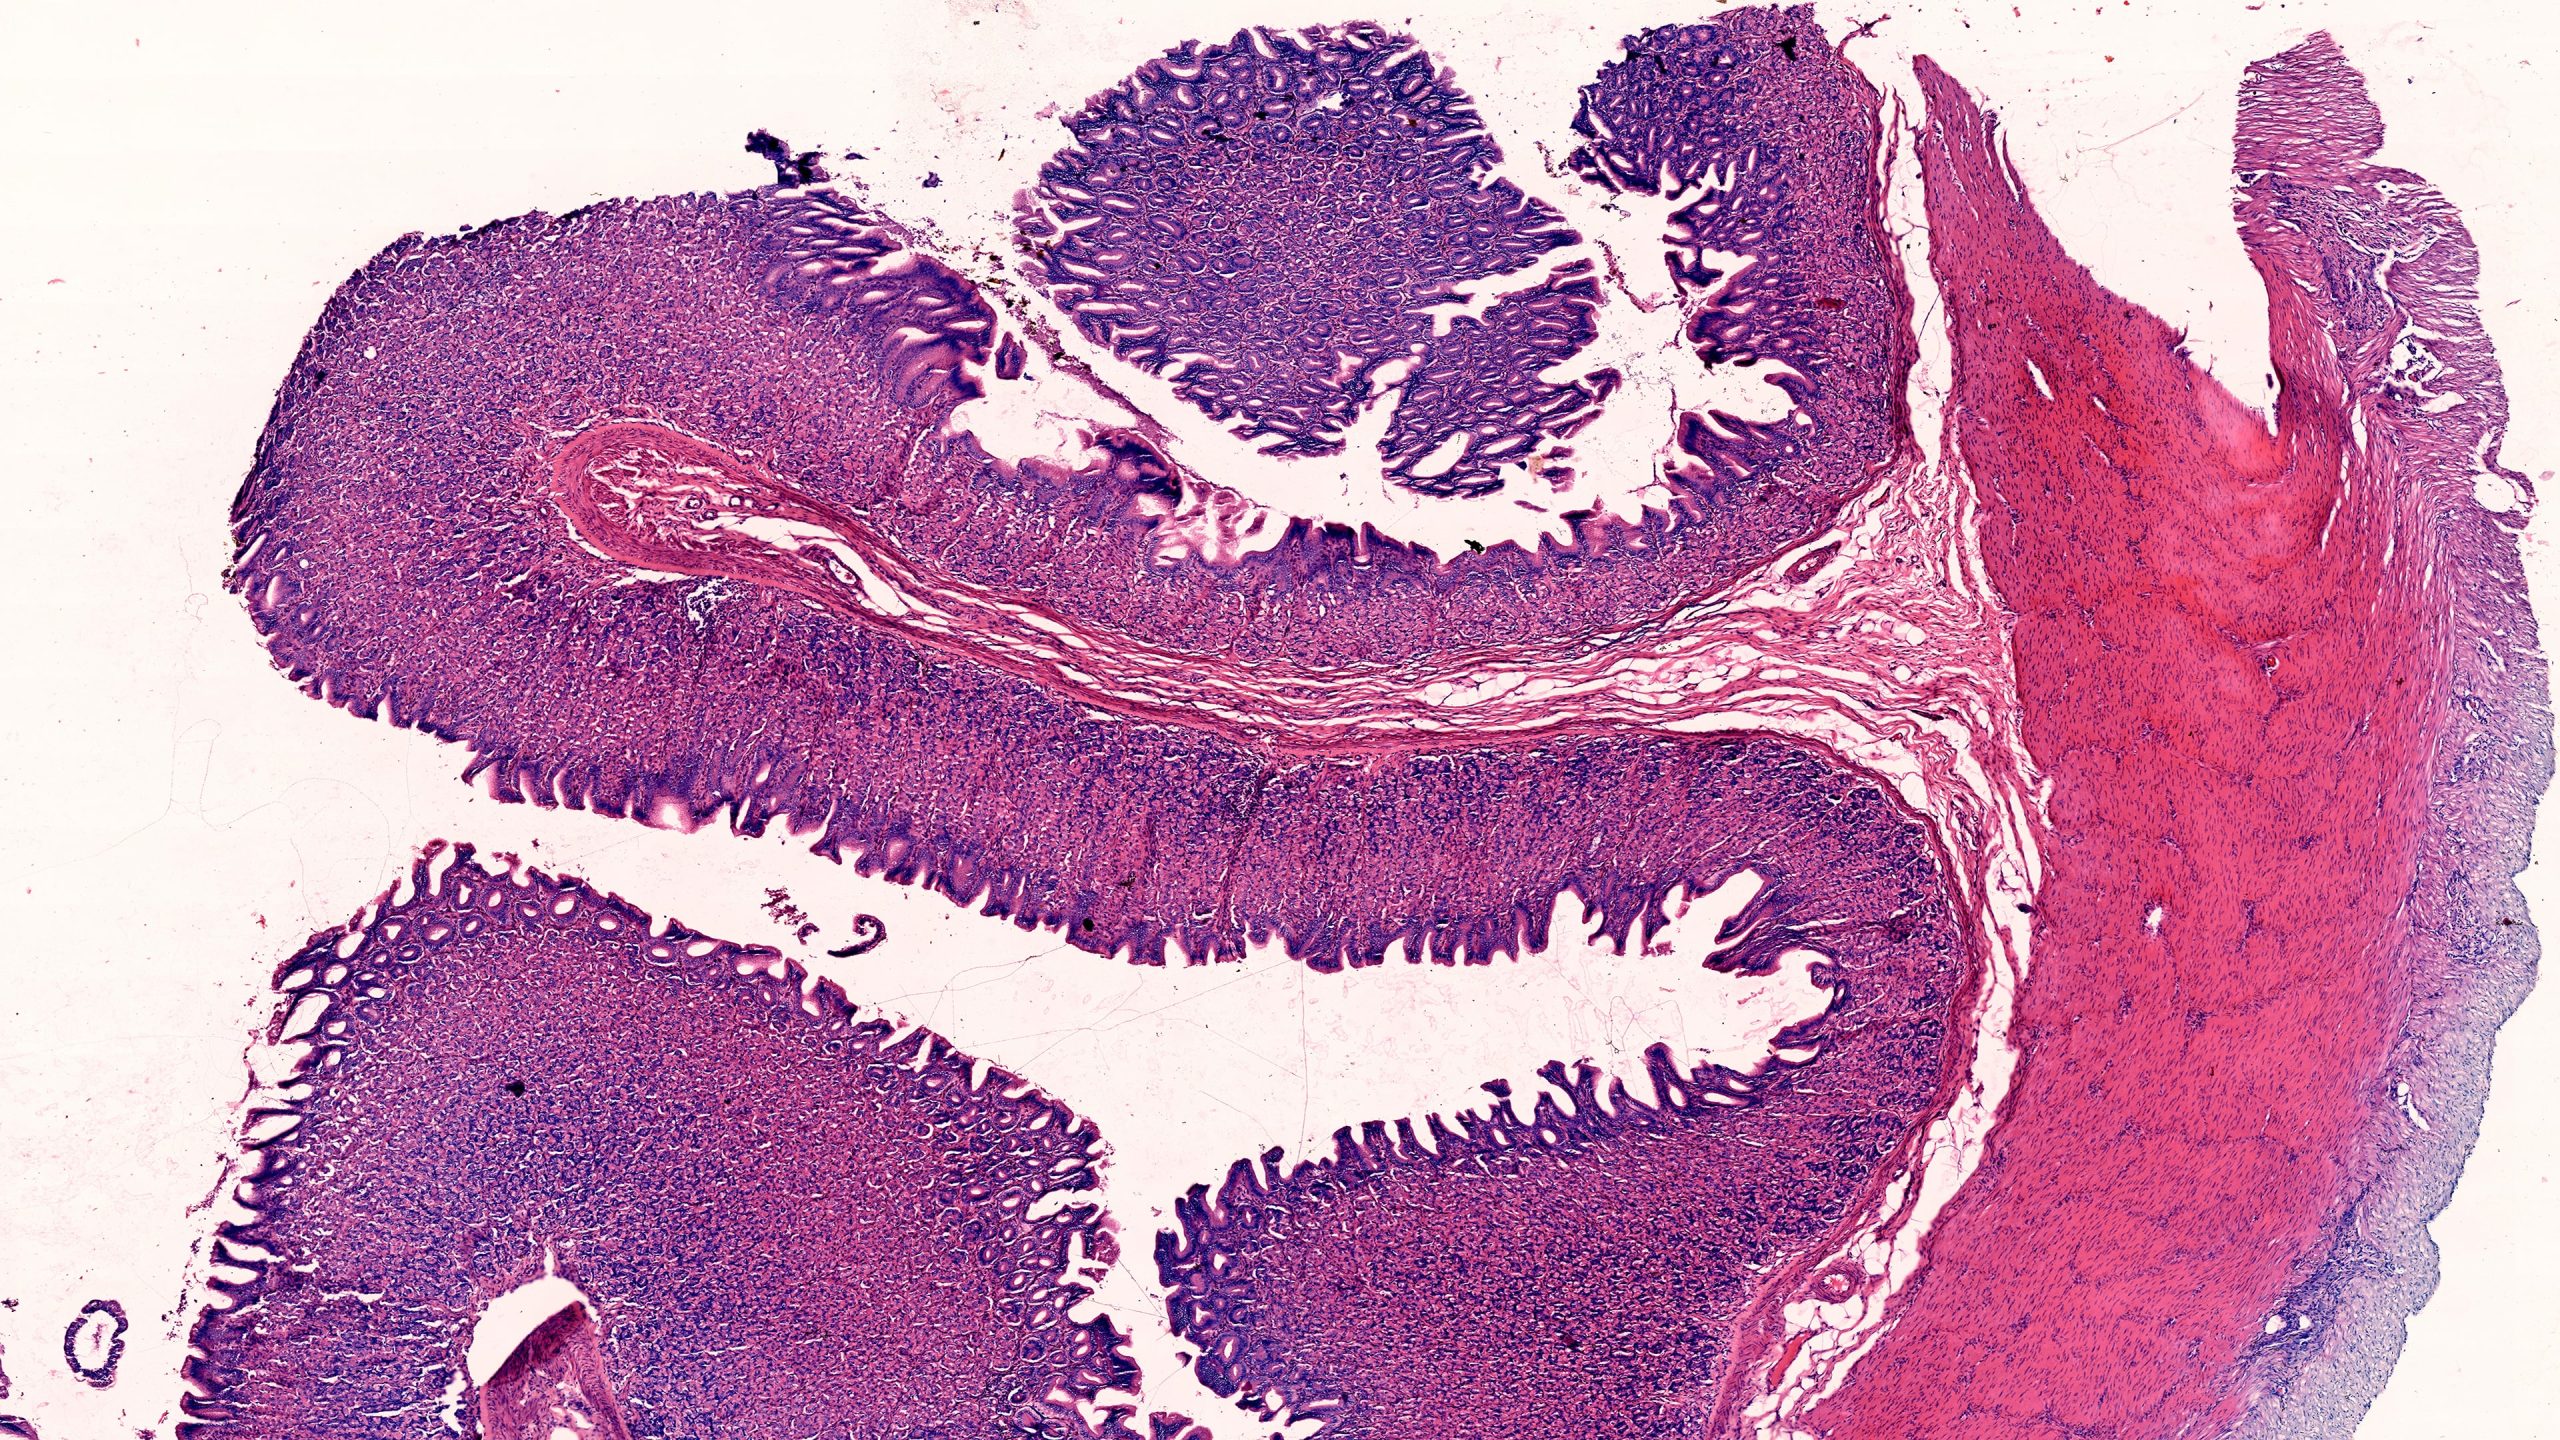

Stomach Pylorus 10X